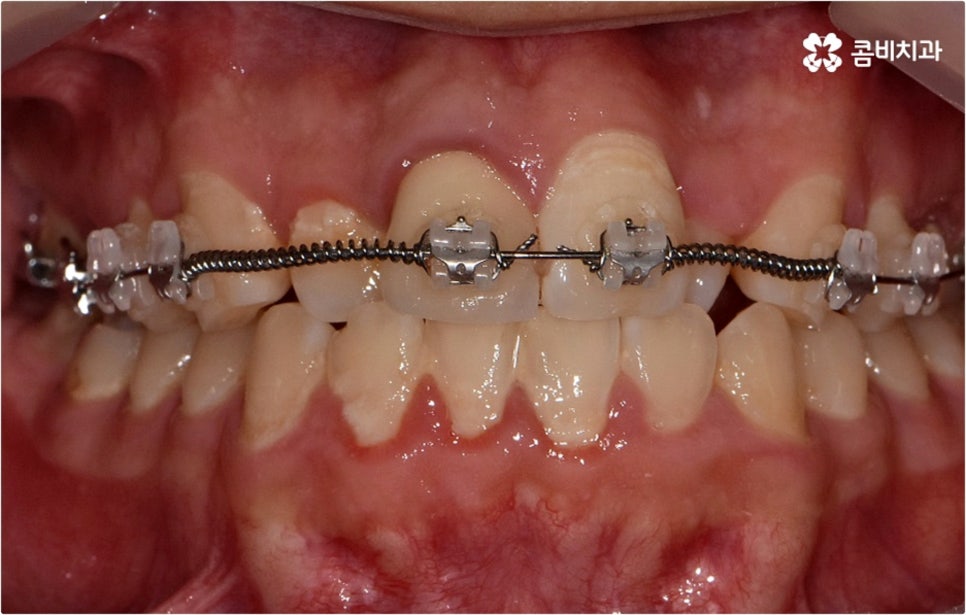

요즘은 관련 치의학 기술이 많이 발달하고 장치도 다양해져서 교정 치료가 예전보다는 훨씬 더 대중화 되었다고 볼 수 있으나 그럼에도 불구하고 막상 덧니교정 을 시작하려고 하면 오래 걸리는 시간이나 치아 이동 통증, 비용적인 부담 등의 이유로 망설여지는 분들도 있을 거예요. 또한 덧니교정 의 적기가 따로 있는지, 덧니를 교정할때 반드시 치아를 발치하는지에 대해서도 자주 문의를 주시고 있는데요.

덧니교정 시 환자분들의 상황에 따라 치아 이동에 필요한 공간이 부족하지 않다면 비발치 교정이 가능한데요, 이런 경우 치아 사이를 살짝 갈아서 여유 공간을 만드는 치간 삭제 방법, 마지막 어금니를 후방으로 이동시키는 방법, 그리고 악궁 확장 장치를 사용해 치아 사이를 벌려주는 방법 등 다양한 방법으로 공간을 만들어 치열을 가지런하게 바로잡아 줄 수 있습니다. 이때 환자분들의 구강 상태, 즉 악궁 크기 대비 치아의 크기, 치아가 겹친 정도, 덧니의 위치와 개수 등을 자세하게 검진한 다음 치아가 이동할 충분한 공간이 확보되지 않는다면 발치 교정을 하게 될 거예요.

정밀 검진 후 상담을 통해 덧니교정 치료 계획을 자세하게 듣고 중간 중간 진행 과정에 대한 브리핑을 받는 등 담당의 선생님과 지속적으로 소통하게 된다면 1~2년 정도 비교적 오래 걸리는 기간 동안 보다 편안한 마음으로 치료에 임하실 수 있으실 거예요. 이를 위해 3D CT 같은 정밀 진단 장비를 갖추고 있는지, 처음부터 끝까지 의료진의 변화없이 책임 진료하는지 꼼꼼히 따져보고 치과를 선택하는 게 필요하다고 할 수 있어요.

또한 교정 치료는 사후 관리도 굉장히 중요하기 때문에 치과에서 정해준 시간 만큼 유지 장치를 잘 착용하지 않으면 치아가 원래 자리로 돌아가서 부정교합이 다시 생길 수도 있고 검진이나 스케일링 등 구강 관리에 부주의하면 주변 잇몸이 약해지면서 치주 질환이 생기기 쉬우니 이런 점들에 주의하시고 시기에 맞춰 내원하셔서 치과 케어 시스템의 도움을 받으시길 권유드리고 있습니다.